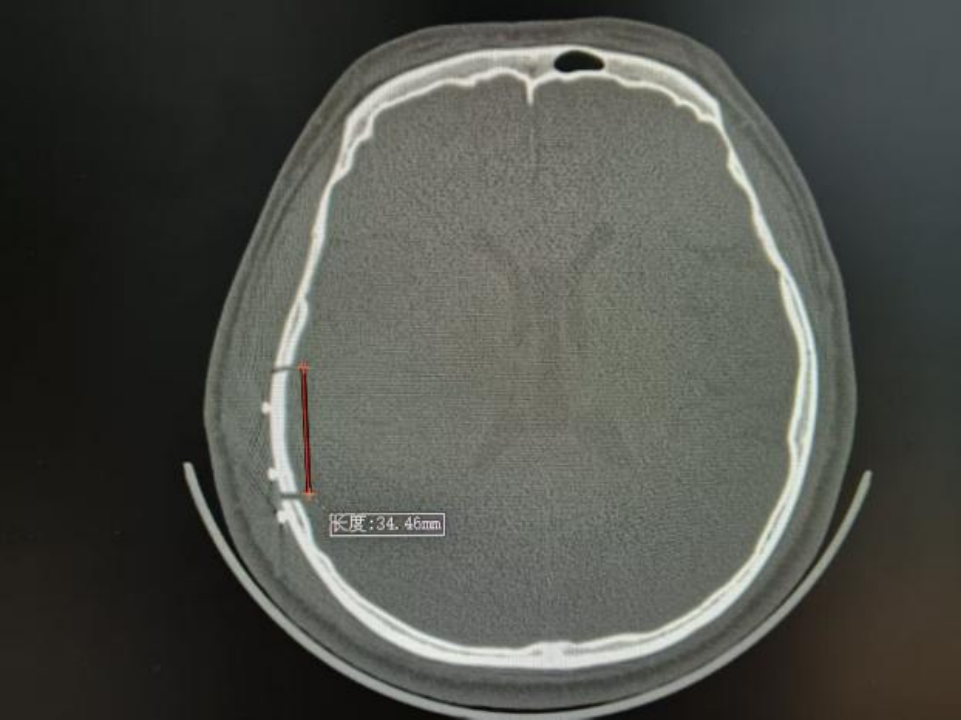

△术后颅脑CT

近期,北大人民青岛医院神经外科团队在北京大学人民医院神经外科专家刘波带领下,常态化开展神经内镜下硬脑膜外血肿清除术。其中一位19岁的年轻小伙,驾驶摩托车不慎摔伤,伤后头痛、头晕、恶心,头痛呈进行性加重,逐渐开始出现意识障碍,到青岛医院急诊行颅脑CT检查后证实为创伤性硬脑膜外血肿,神经外科团队予以急症状态下神经内镜下硬脑膜外血肿清除术手术治疗,目前患者已经康复出院。